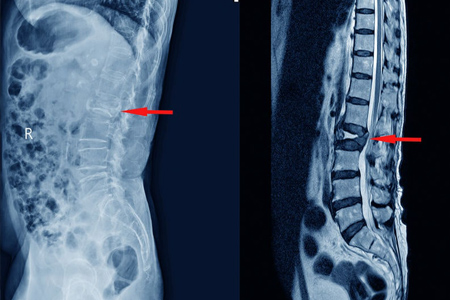

• Radiografía Con una simple radiografía basta para apreciar un aplastamiento vertebral, la radiografía tiene como limitación que no permite distinguir entre un aplastamiento reciente de un aplastamiento crónico.

• TAC El Tac nos permite analizar el aplastamiento vertebral con más detalle. Con un Tac podemos ver si el muro posterior de la vértebra está afectado, si el aplastamiento es central o lateral o si hay fenómeno de vacío (aire en el interior de la vértebra).

• Resonancia magnética La resonancia es la mejor prueba para valorar si una fractura es aguda o ya está curada. También nos ayuda a saber si fracturas antiguas continúan con edema lo que es indicativo de que aún pueden ser dolorosas y por tanto serían susceptibles de ser tratadas.